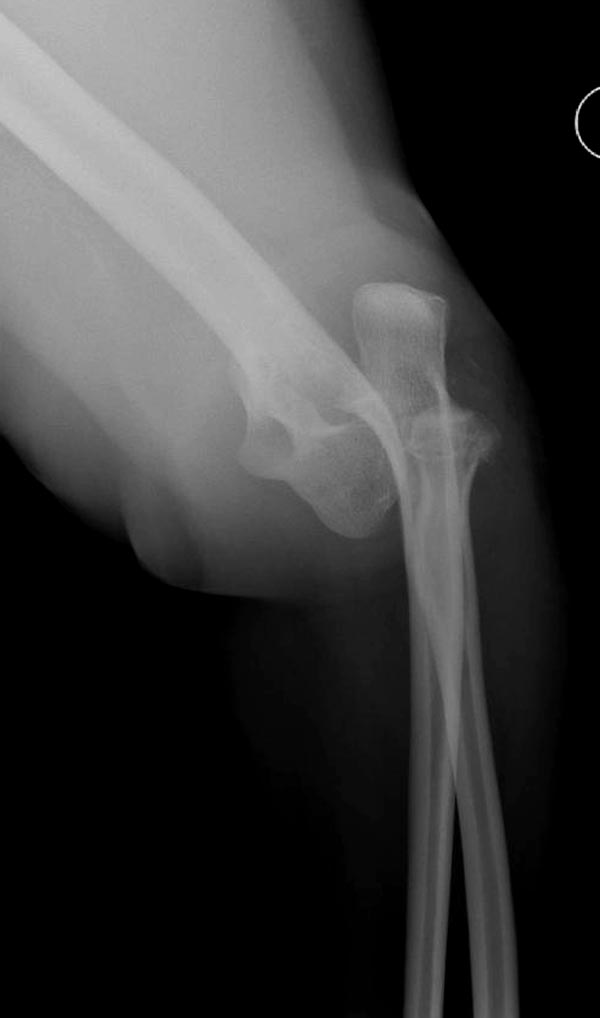

Имя     : 2 Elbow radial head fx.JPG

Тип     : image/jpeg